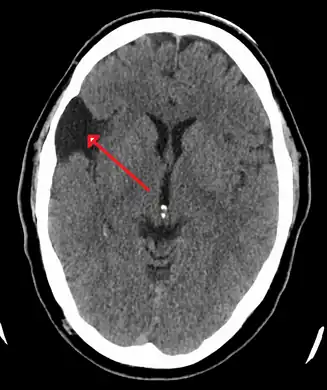

-

Male with complicated arachnoid cyst -

Arachnoid cyst as seen on a CT image of the brain -

Axial CT showing a typical arachnoid cyst left temporal